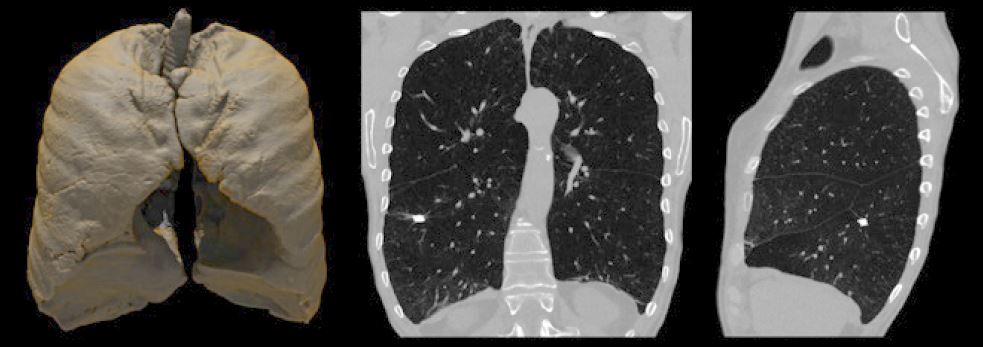

Сканування з SilverBeam із кальцинованим вогнищем у правій нижній частці.

Після успішного впровадження Advanced intelligent Clear-IQ Engine (AiCE), Precise IQ Engine (PIQE) це наступний крок у реконструкції глибокого навчання, який поєднує надзвичайну просторову роздільну здатність і знижений шум. PIQE показує чіткіші анатомічні деталі в

матриці зображення 1024 для кращого окреслення невеликих анатомічних структур для більш точної діагностики складних патологій, особливо в кардіології, онкології або педіатричної візуалізації зображення 1024 для кращого окреслення невеликих анатомічних структур для більш точної діагностики складних патологій, особливо в кардіологічної, онкологічної або педіатричної візуалізації.